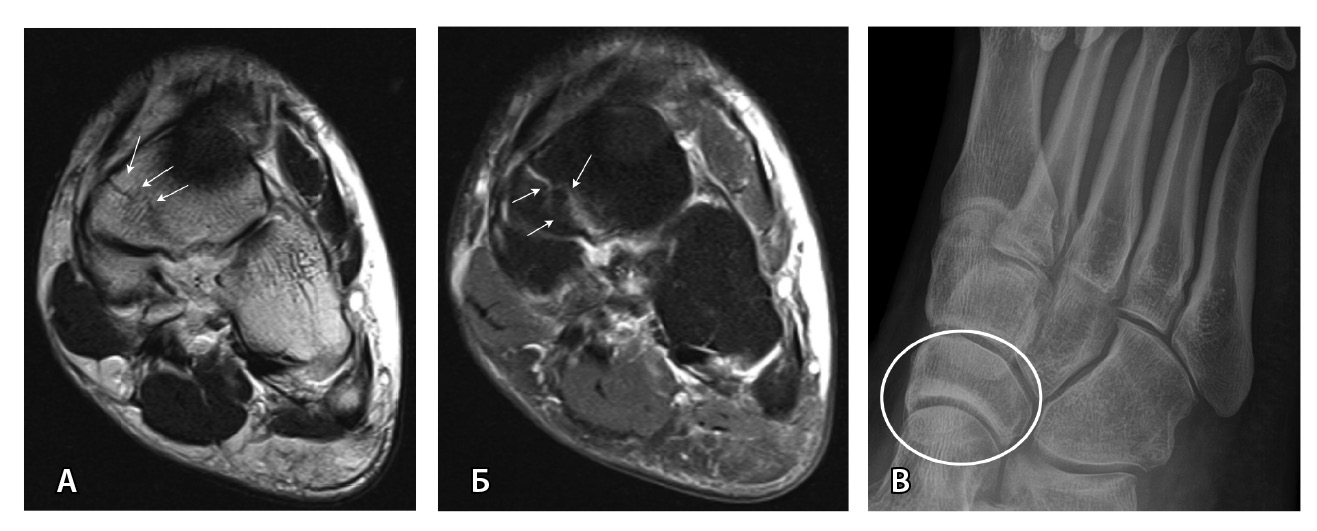

МРТ – наиболее подходящий метод визуализации остеохондрального повреждения купола таранной кости с чувствительностью и специфичностью 96% [52]. В исследованиях M. Haubro и соавт. [53], M. P. Wilson и соавт. [28] МРТ квалифицирована как золотой стандарт диагностики скрытых переломов по сравнению с КТ и рентгенографией. Протокол, состоящий из корональных T1-взвешенных изображений и STIR, обладает 100% чувствительностью в выявлении рентгеннегативных переломов (рис. 3) [28].

Рис. 3. Рентгеннегативный перелом ладьевидной кости: А – Т2-взвешенное изображение, аксиальная плоскость; Б – PD-FS-взвешенное изображение, аксиальная плоскость (стрелками указана линия перелома); В – рентгенография (кругом отмечена область перелома)